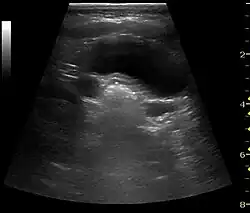

In the longitudinal scan plane, the kidney has the characteristic oval bean-shape. The right kidney is often found more caudally and is slimmer than the left kidney, which may have a so-called dromedary hump due to its proximity to the spleen. The kidney is surrounded by a capsule separating the kidney from the echogenic perirenal fat, which is seen as a thin linear structure.[1]

The kidney is divided into parenchyma and renal sinus. The renal sinus is hyperechoic and is composed of calyces, the renal pelvis, fat and the major intrarenal vessels. In the normal kidney, the urinary collecting system in the renal sinus is not visible, but it creates a heteroechoic appearance with the interposed fat and vessels. The parenchyma is more hypoechoic and homogenous and is divided into the outermost cortex and the innermost and slightly less echogenic medullary pyramids. Between the pyramids are the cortical infoldings, called columns of Bertin (Figure 1). In the pediatric patient, it is easier to differentiate the hypoechoic medullar pyramids from the more echogenic peripheral zone of the cortex in the parenchyma rim, as well as the columns of Bertin (Figure 2).[1]

Figure 1. Normal adult kidney. Measurement of kidney length on the US image is illustrated by '+' and a dashed line. *Column of Bertin; ** pyramid; *** cortex; **** sinus.[1]